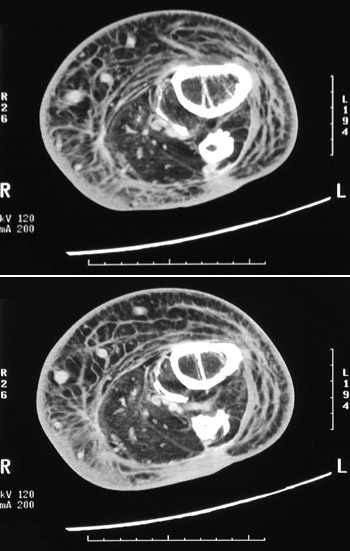

This CT scan of the leg demonstrates a healing fracture of the mid-tibia. Note the thickened bone cortex and the callus extending across the marrow cavity.